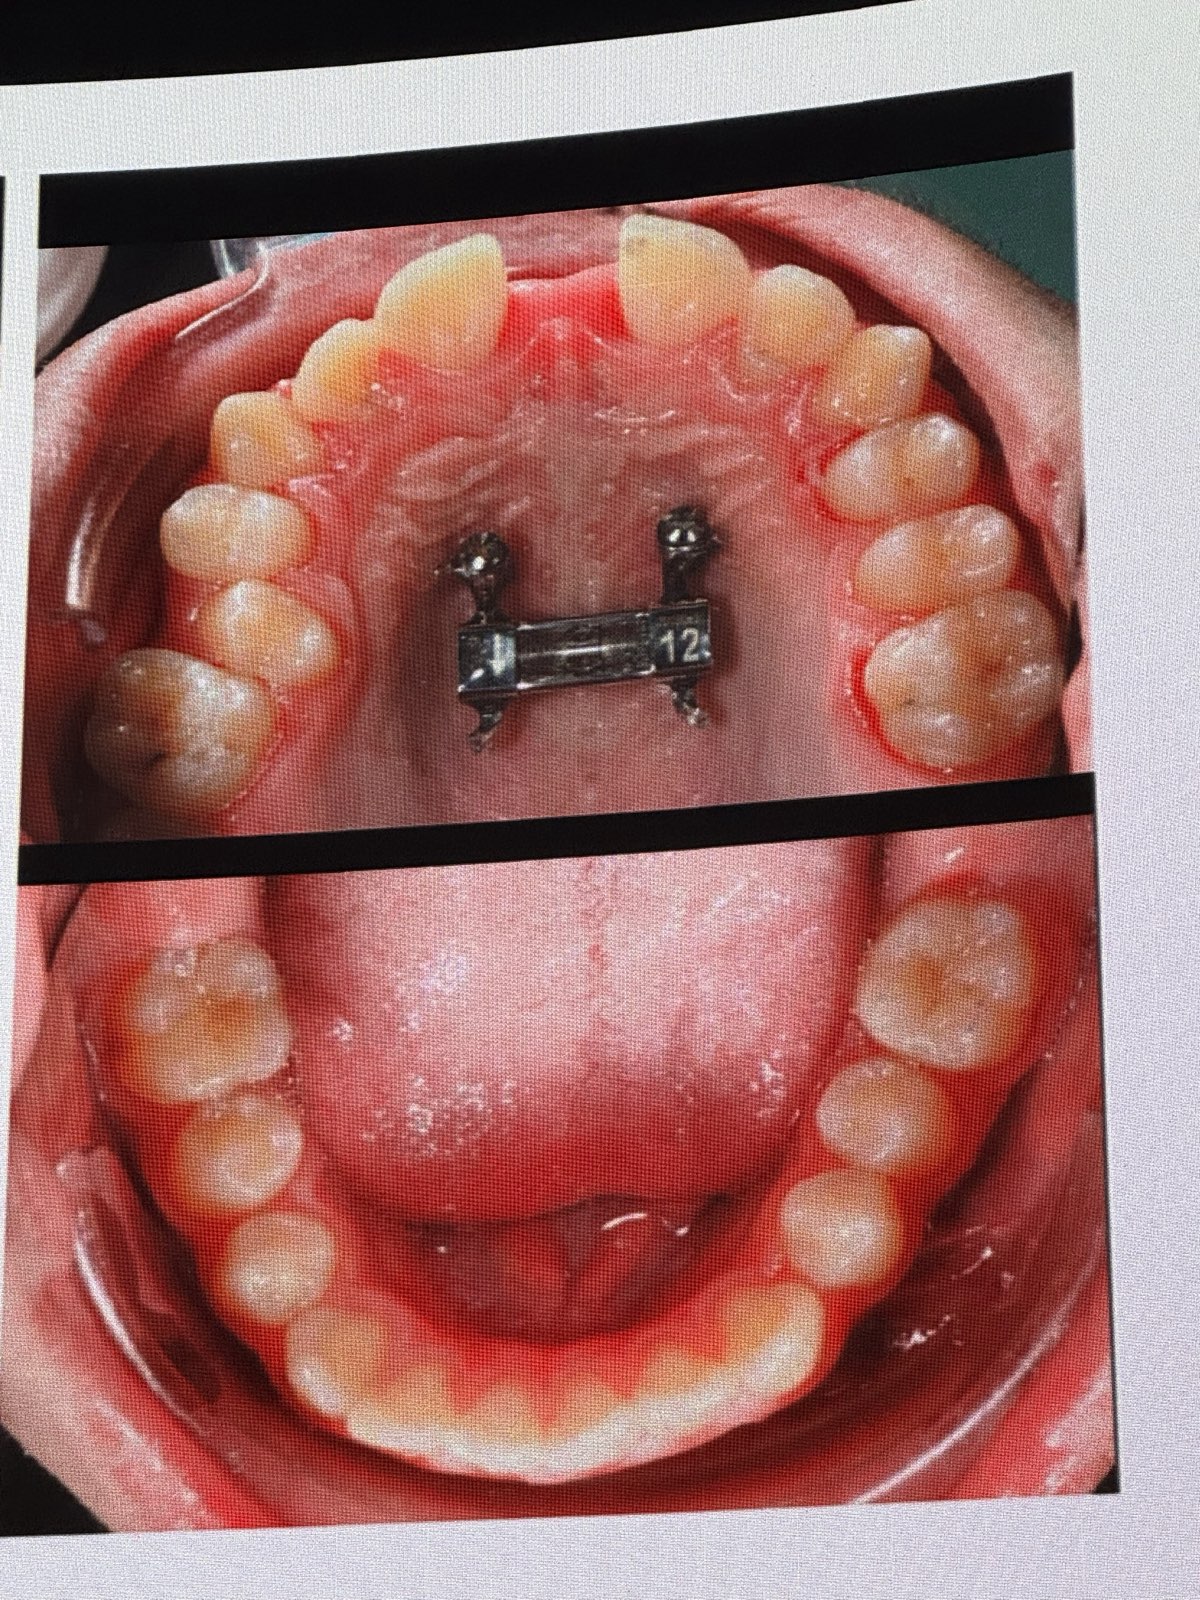

• アライナー矯正における圧下のアプローチ

• 叢生(crowding)がなく圧下が必要な場合、アタッチメントよりも「イントルージョンリッジ(Intrusion Ridge)の使用を好む。

• 「ステージ12」(アライナーの交換時期)で、犬歯と側切歯間にアタッチメントを追加し、エラスティックをかけて上顎前歯全体を圧下する症例。